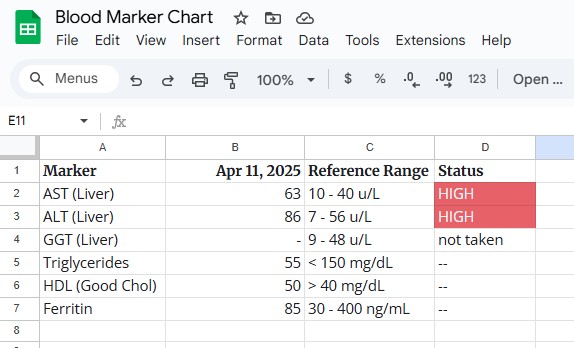

The Baseline Data

I believe in tracking progress, not just guessing. Here is exactly where I started.

My Bloodwork (Pre-Intervention):